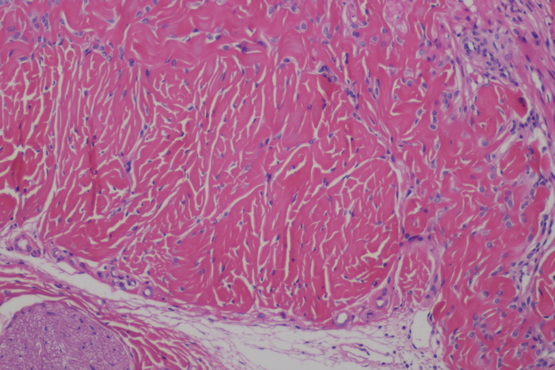

HE染色是目前国内外病理诊断上广泛采用的常规染色方法。HE染色即苏木精-伊红染色法( hematoxylin-eosin staining ),是石蜡切片技术里常用的染色法之一。苏木精染液为碱性,主要使细胞核内的染色质与胞质内的核糖体着紫蓝色;伊红为酸性染料,主要使细胞质和细胞外基质中的成分着红色。一张做工精良的HE切片是病理医生得以做出正确诊断的关键。而一台性能优良的显微镜和成像清晰的摄像头则是病理医生做出正确诊断的最重要的工具。生物显微镜ML31用于HE染色观察,具有易用舒适,稳定可靠的优势。

近期,明美广州区域安装生物显微镜ML31搭配630万像素显微镜相机MS60,用于HE染色片的观察并能清晰拍照。在显微镜下做诊断其实并不容易,这需要大量知识的学习和丰富的经验积累,而好的显微镜能有效提升效率,ML31采用高平场性物镜,保证10X/22视野数下的平坦清晰成像。